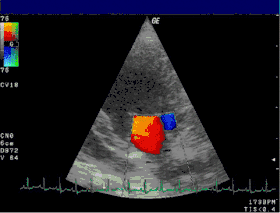

تخطيط صدى القلب الدوبلري

الدوبلر الطبي أو الإيكو دوبلر هو نوع من أنواع التصوير الطبي للأوعية الدموية يتم عن طريق استخدام الموجات فوق الصوتية،[1] ويهتم بتشخيص وتقييم الأوعية الدموية من تضيق وانسداد وانسلاخ وتوسع وغيره. يرجع الفضل في اكتشاف الدوبلر بشكل عام إلى العالم النمساوي كريستيان دوبلر. ولذلك سمي الإيكو دوبلر بهذا الاسم تخليدا له، حيث كان له دور كبير في دراسة الأمواج الصوتية. يمكن لبعض أجهزة الإيكو أن تستخدم كإيكو عادي أو كإيكو دوبلر في نفس الوقت وذلك بتغيير البروب فقط. ويعتبر الدوبلر في الزمن الحالي من أفضل الفحوصات لتصوير الأوعية الدموية وتقييمها لعدة أسباب منها:

- دراسة جريان الدم عبر صمامات القلب وهي الصمام التاجي ومثلث الشرف والأبهري والرئوي وتشخيص قصور أو تضيق هذه الصمامات.

- يبين اتجاه الدم ويقيس مدة الانعكاس إن وجدت.